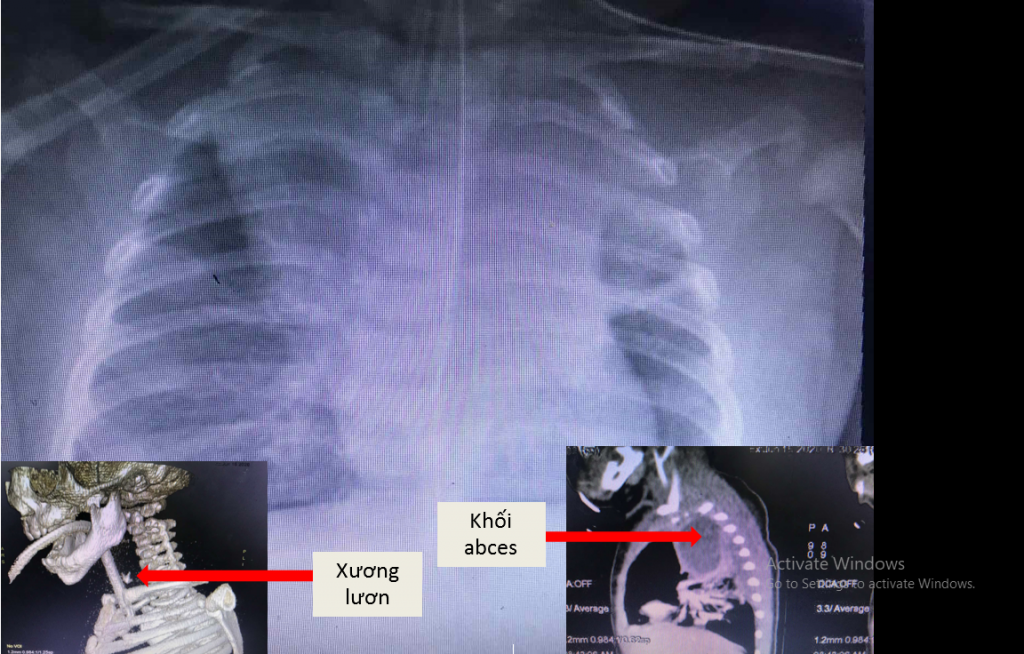

Bé trai thủng thực quản vì mẹ nấu cháo lươn cho ăn dặm ảnh 1Mảnh xương lươn cắm chặt trong thành thực quản và ổ áp xe (ảnh: BVCC)

Trẻ được đặt lại nội khí quản giúp thở, thở máy, chụp Xquang phổi và CT scan ngực ghi nhận trẻ bị áp xe thành sau họng lan xuống 1/3 trung thất sau, viêm phổi, trên hình ảnh tạo hình ghi nhận có dị vật ở thực quản và đường dò từ thực quản ra khối áp xe.

Ngay lập tức, bệnh nhi được hội chẩn bởi ê-kíp hô hấp – tiêu hóa – tai mũi họng, ngoại lồng ngực tiến hành rạch cạnh cổ thoát lưu mủ khối abces, nội soi gắp ra được mảnh xương lươn (0,5×0,3cm) gắm sâu vào thành thực quản và ghi nhận thực quản rách một đoạn 2cm năm ở 1/3 giữa thực quản, khó khăn cho các phẫu thuật viên khâu vá lại. Trẻ được đặt dẫn lưu cạnh cổ, đặt ống thông dạ dày dẫn lưu, đặt ống thông hỗng tràng ra da để nuôi ăn và dung kháng sinh phổ rộng.